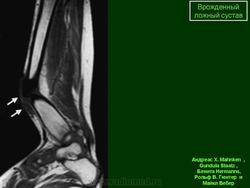

Врожденный ложный сустав проявляется в 2 формах: истинного и латентного, или несостоявшегося, ложного сустава. Истинный ложный сустав голени обнаруживается при рождении ребенка в виде значительной угловой деформации, укорочения сегмента, подвижности отломков на месте деформации; латентный ложный сустав проявляется наличием деформации костей голени в нижней трети, склерозом на месте искривления. Причиной возникновения истинного ложного сустава чаще всего служит незначительная травма или хирургическое вмешательство, направленное на устранение искривления большеберцовой кости. У многих больных с врожденными ложными суставами имеется сопутствующее укорочение, иногда достигающее 10—12 см. Кроме того, у ряда больных выявляется недоразвитие малоберцовой кости и голеностопного сустава.

Клинико-рентгенологические исследования позволяют выявить тугие и подвижные ложные суставы. При тугих ложных суставах имеются гипертрофированные фрагменты с выраженным склерозом, сами фрагменты выше и ниже склерозированной зоны остеопорозны. При подвижных ложных суставах концы кости истончены, остеопорозны, зона склероза выражена в меньшей степени. Возможны угловые деформации как при той, так и при другой формах на уровне патологической зоны. При разболтанных ложных суставах патологическая подвижность резко выражена, при тугих — определяется в виде легких качательных движений.

Рентгенологические признаки: щель между отломками, атрофия отломков и склероз их концов, заращение костномозгового канала (замыкающая пластинка), иногда — остеопороз.